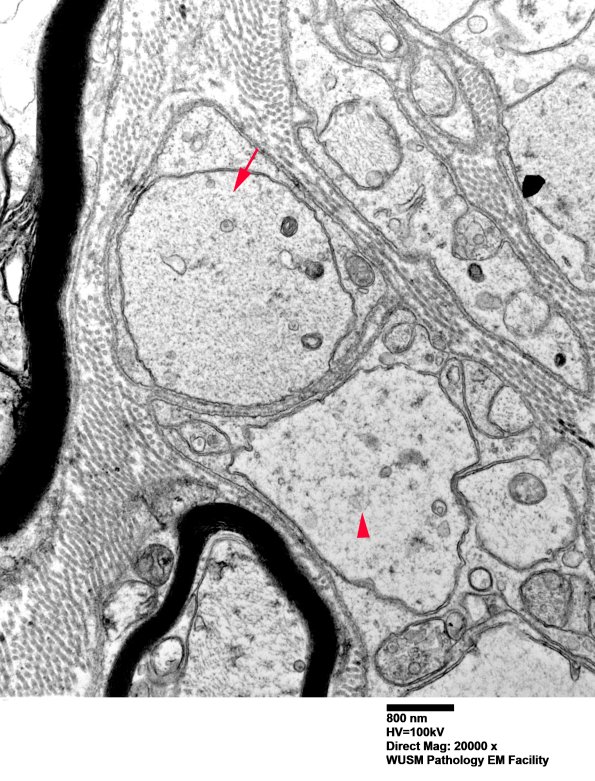

The large structure marked with an arrow appears to be a pre-myelinated axon; however, the structure marked with an arrowhead appears to have some subtle degenerative changes. (electron micrograph)